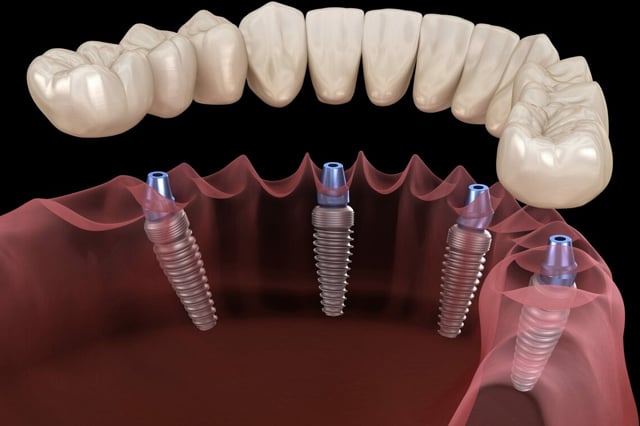

Implantes eficazes e seguros

Indicados para reabilitações complexas, os implantes zigomáticos proporcionam máxima estabilidade e segurança. São uma solução moderna, segura e altamente eficaz para devolver não apenas o sorriso, mas também a autoestima e a qualidade de vida de quem necessita de suporte adicional com 98% de taxa de sucesso

O All on Four é uma técnica moderna e segura que permite reabilitar arcadas inteiras com apenas 4 implantes por arcada e uma prótese fixa instalada em até 72 horas. Ideal para quem perdeu todos os dentes ou usa dentadura e deseja um sorriso firme, bonito e natural em poucos dias.